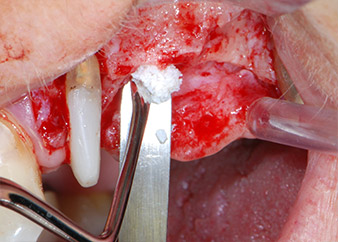

Avant la pose de l'implant, les tissus infectés ont été retirés de l'os alvéolaire sur le site de l'implant et autour des dents piliers à l'aide d'un insert initialement conçu pour le façonnage de l'os et la récupération des copeaux d'os (Piezomed, insert B5) (Figures 6 et 7).

Avant la mise en place de l'implant, et après vérification de l'intégrité de la membrane de Schneider (Fig. 9), le plancher sinusien interne a été élevé sur les deux sites d'implantation à l'aide d'un matériau de substitution osseuse xénogénique (Bio-Oss, Geistlich Biomaterials) (Fig. 10).

Les défauts osseux autour des implants, sur la face mésiale de la dent 27 et autour de la racine de la dent 24, ont été reconstruits par des particules de substitut osseux xénogénique et recouverts d'une membrane collagène résorbable (Bio-Gide, Geistlich Biomaterials) pour une augmentation par GBR (Fig. 13 et 14).